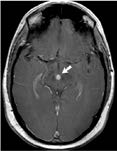

Skilled neurosurgeons at Georgia Regents Medical Center are able to apply this advanced technology to destroy brain tumors and malformed blood vessels without opening the skull. Treatment is simple, painless, and fast. Gamma Knife, a targeted form of radiation therapy, earned its name based upon its scalpel-like precision. With Gamma Knife, incisions are not required and the procedure is usually performed without anesthesia. Generally, the patient's family can accompany them during the majority of the procedure and patients can usually return to preoperative lifestyle the same day.

- Blood vessel abnormalities such as ArterioVenous Malformations (AVMs)